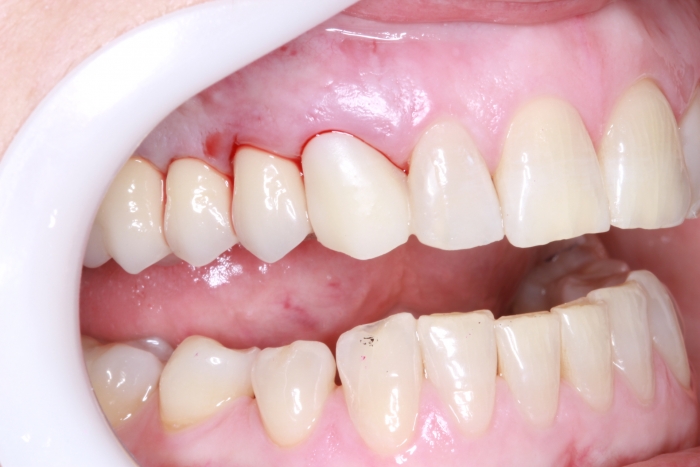

Foto lateral com protese definitiva 22-08-17 - Clínica Cliniface

Foto lateral com protese definitiva 22-08-17